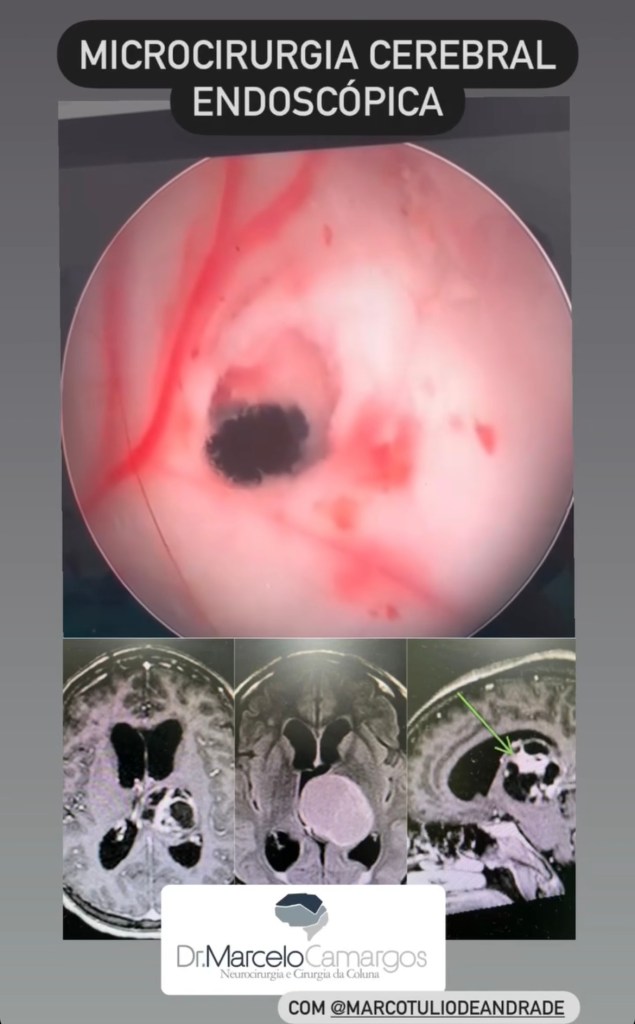

GALERIA De cirurgias

Abaixo você pode conferir imagens de algumas cirurgias já realizadas por Dr. Marcelo Camargos. Caso tenha alguma dúvida ou interesse, não deixe de fazer contato para maiores esclarecimentos!